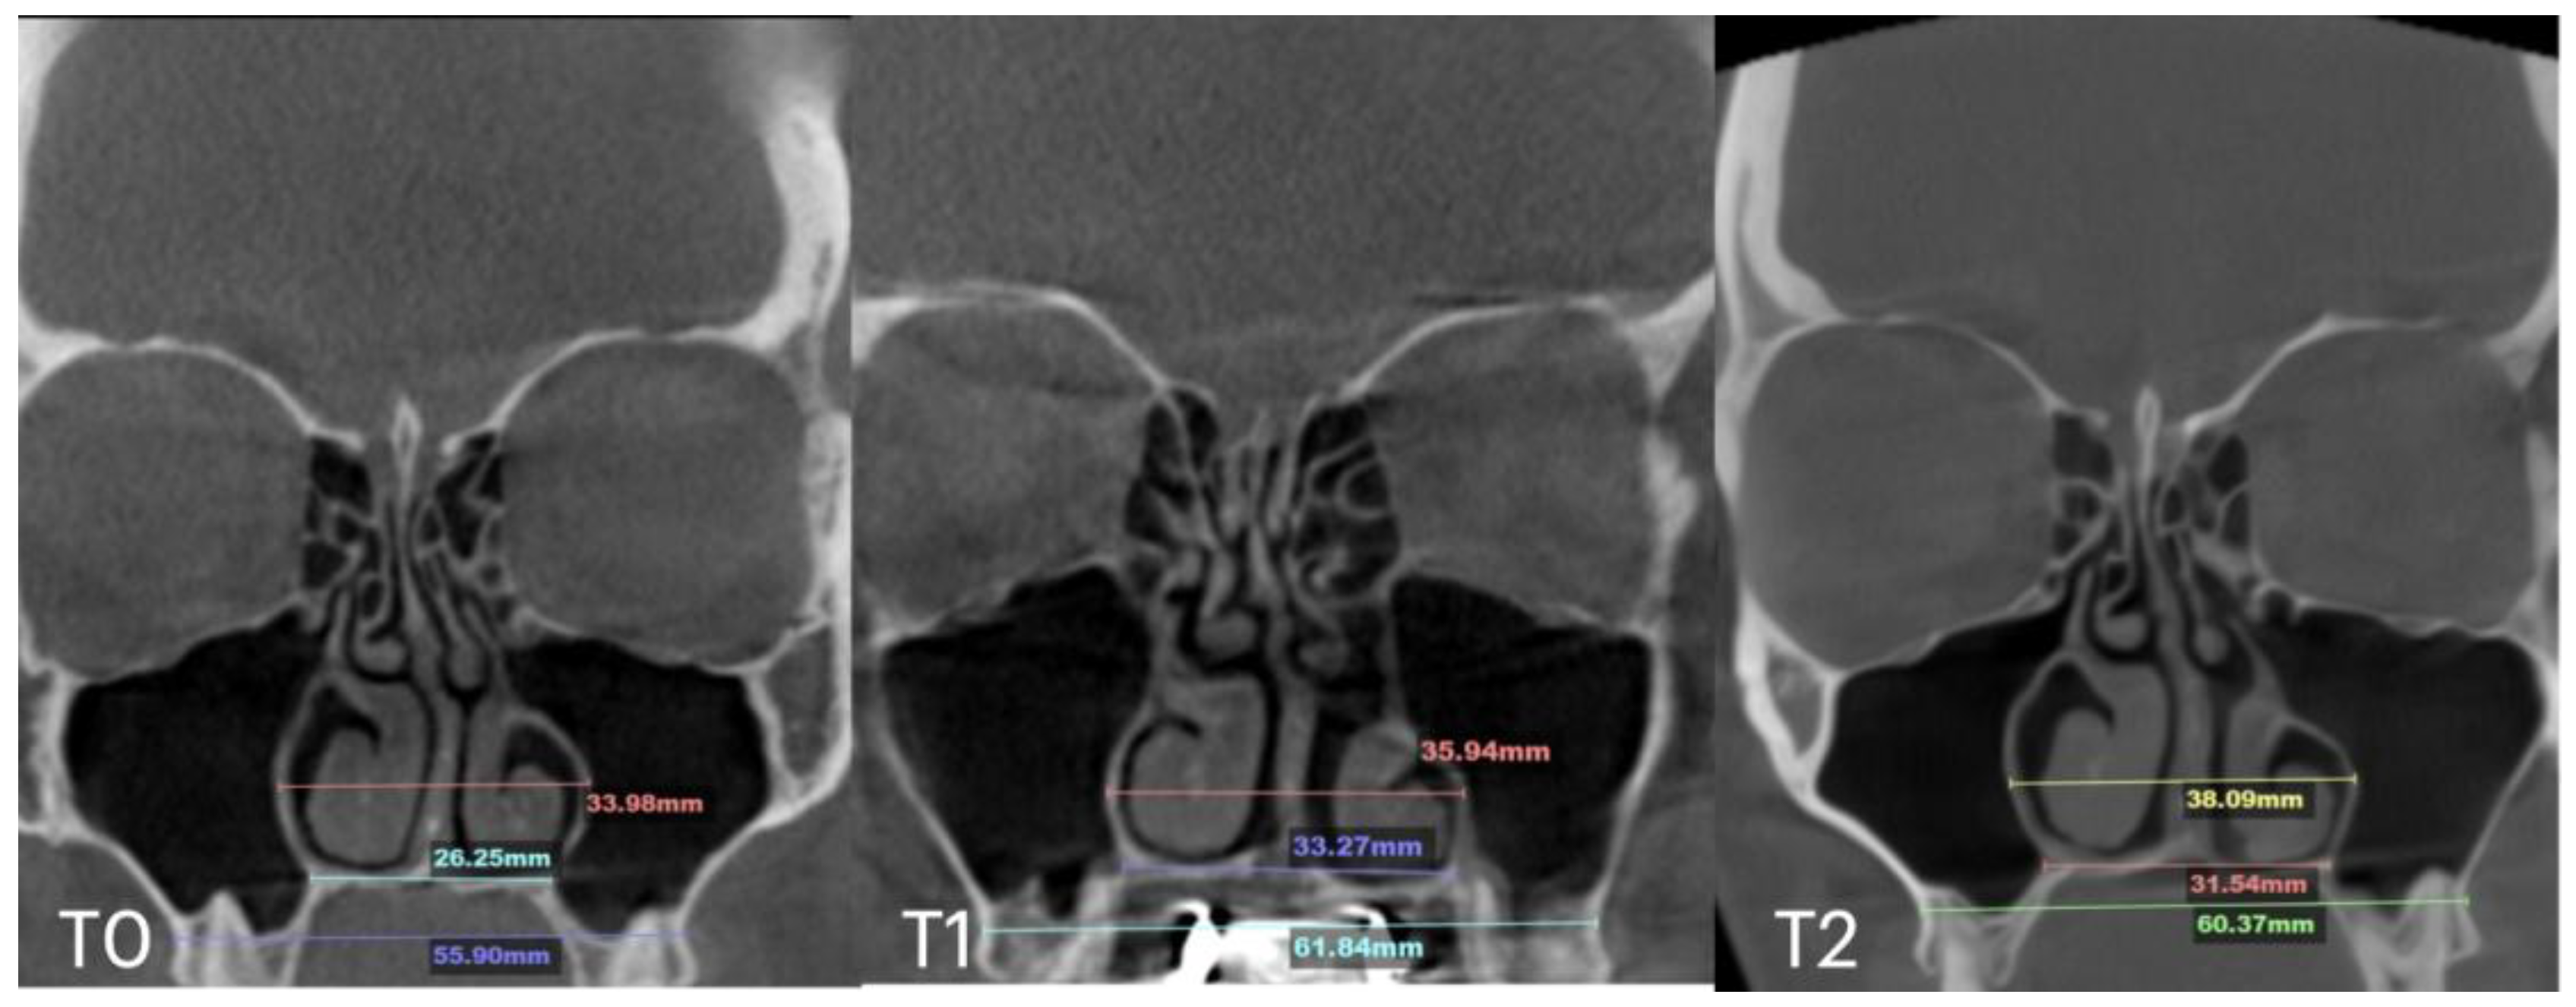

| Case D | 26.25 | 33.27 | 31.54 | 55.9 | 61.84 | 60.37 | 33.98 | 35.94 | 38.09 | 29.77 | 29.24 | 29.02 | 6.2 |